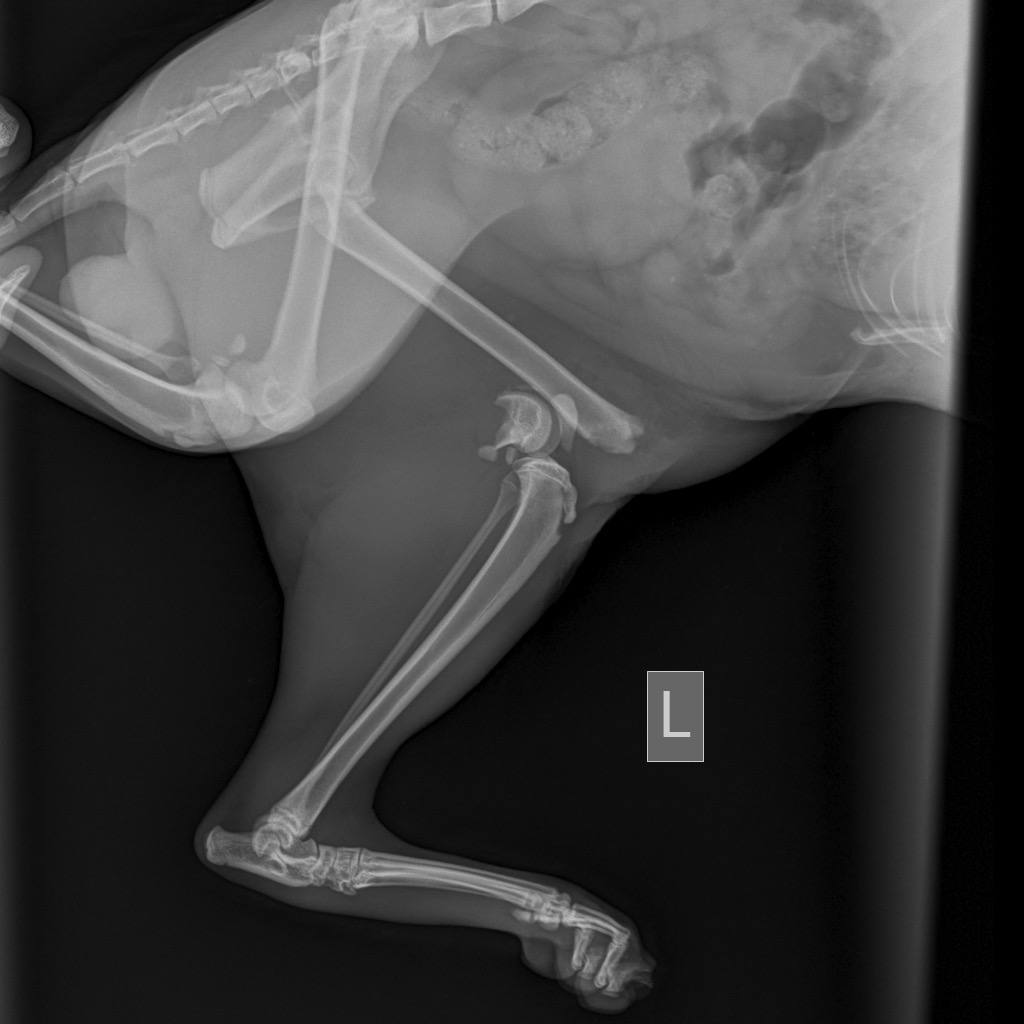

В прошлое воскресенье, молодые люди нашли котика с перебитыми задними лапами. Не смогли пройти мимо, и оставить красавца на верную смерть. Повезли в клинику. Анализы, обследования, осмотры. У котейки не нашли инфекций, но с лапками беда. Сложные переломы, и единственный выход, это остеосинтез. Начали поиск клиник и хирургов которые проведут операцию. Цены озвучивались от 40 до 100 тысяч за одну лапку(. Но ребята не сдавались, и продолжали поиски. Параллельно обратились в различные фонды, но во всех получили отказ.

И всё же, молодые люди смогли найти хирурга, который согласился прооперировать котана за 50 т. обе лапы. Плюс ОРИТ минимум на неделю. А это ещё 10 т. в сутки.

Вчера была проведена операция. Всё прошло не плохо. Коту дополнительно поставили стому, что бы докармливать. Но после операции начал падать гематокрит и эритроциты. Нужно переливание крови.